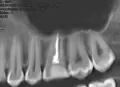

Начал разрушаться зуб, верхняя левая 6. Обратился к стоматологу. Сделали рентген, высверлили каналы, в общем, за несколько походов мне его нарастили.

Не имея данных рентгенологического исследования, могу предположить хроническое воспаление на корнях (периодонтит), либо патологический зубодесневой карман.